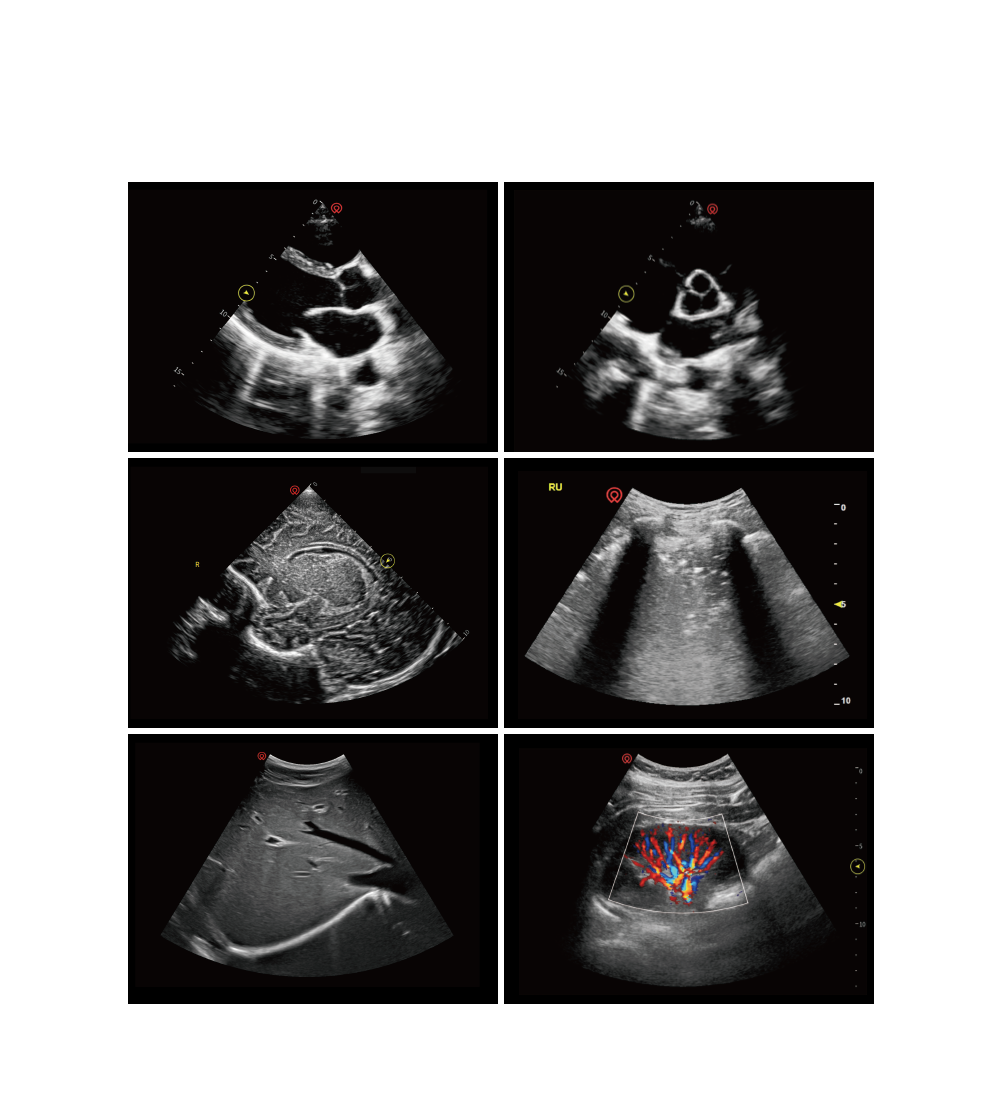

comprehensive probe selection

a versatile range of transducers designed to support cardiac, lung, abdominal, vascular, and musculoskeletal imaging

• optimized for adults, pediatrics and neonates

• tailored to meet multi-site diagnostic needs in emergency care

• enabling fast, accurate evaluations when every second counts

exceptional image quality

application pictures